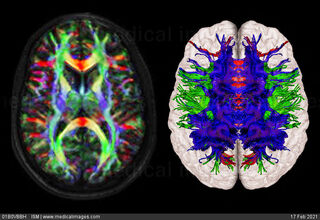

Diffusion tensor imaging (DTI) tractograpy. The color-coding of

Diffusion Tensor Imaging (DTI) - Fiber Tracking - Imagilys

Diffusion Tensor Imaging (DTI) - Fiber Tracking - Imagilys

Diffusion Tensor Imaging (DTI) - Fiber Tracking - Imagilys

A) Diffusion tensor imaging (DTI)-based whole-brain tractogram in